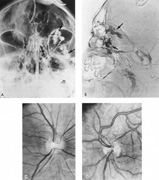

SUPRATENTORIAL

From 85% to 90% of AVMs are in the supratentorial compartment and are supplied primarily by the carotid circulation (Figs. 7 and 8). The remainder are supplied by the vertebrobasilar system. The approximate frequency of location is as follows: frontal, 22%; temporal, 18%; parietal, 27%; occipital, 5%; and deep intraventricular or paraventricular, 18%. The intracerebral site of the malformation does not necessarily indicate that there will be signs referable to that area simply from the mass effect of the malformation. Clinical features primarily result from subarachnoid hemorrhage or intraparenchymal hemorrhage with hematoma formation.

Fig. 7. Supratentorial arteriovenous malformation in a 28-year-old woman with a history of focal motor seizures for many years and a recent subarachnoid hemorrhage. A: Lateral projection carotid arteriogram demonstrating a huge deep hemispheral arteriovenous malformation. B: Frontal projection. C: Fundus photograph showing anomalous tortuous vasculature in each eye. No retinal arteriovenous shunt was detectable.